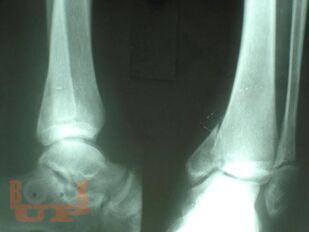

Учебно-методическое пособие содержит необходимую информацию для врачей по вопросам профилактики и лечения последствий тяжелых повреждений области голеностопного сустава. В Пособии представлены условия развития тяжелых статико-динамических осложнений при травмах голеностопного сустава, особенности осложнений при последствиях переломов дистального суставного отдела костей голени. Особое внимание уделено механизму развития посттравматического плоскостопия при повреждениях области голеностопного сустава.

В пособии обобщен более, чем 30-летний опыт лечения пациентов с последствиями тяжелых повреждений области голеностопного сустава.